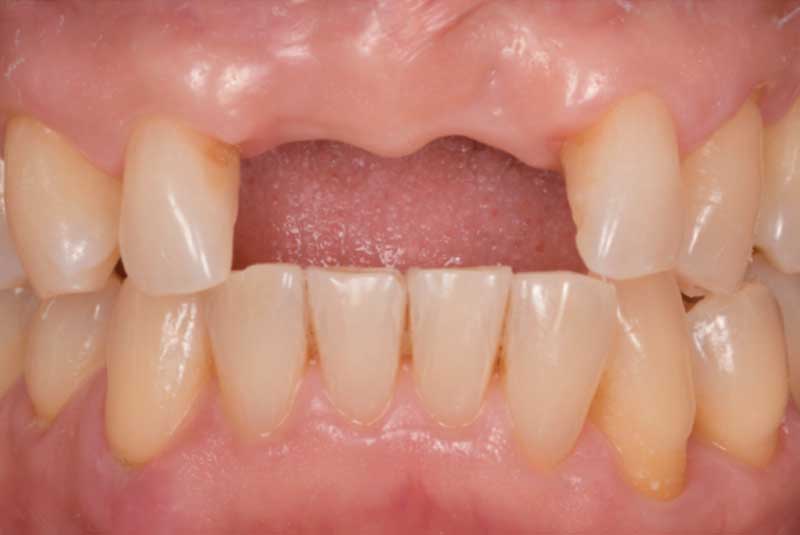

The patient had her implants placed 20 years ago. Four implants, particularly in the maxilla, were not positioned ideally for me to utilize and restore, while the four implants in the mandible were outdated and no longer functional. The patient's primary concern is to restore both function and aesthetics.

All on 6: Facial cut back (PFZ) Zirconia Full arch prosthesis for Maxilla and Mandible Before & After